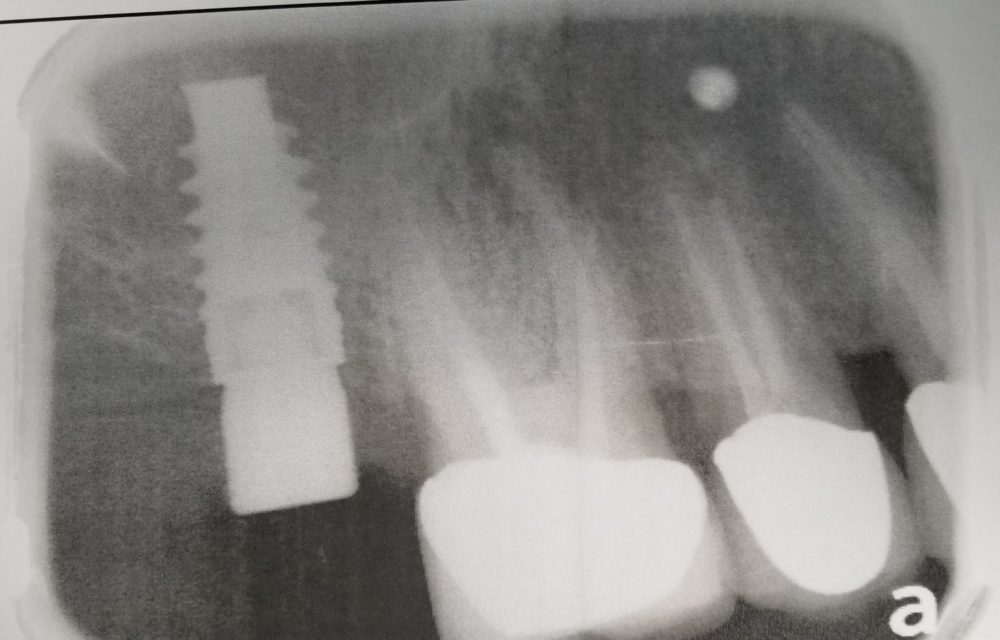

КТ діагностика ротової порожнини

Комп’ютерна томографія зубів – досконалий метод дослідження, який дозволяє лікарю визначати параметри будови зубощелепної системи, що дає більше інформації про аномальні патології. Це відносно нова методика діагностики в галузі стоматології. Але незважаючи на це, за короткий проміжок часу вона стала широко прийнятною.

Комп’ютерна томографія дозволяє отримувати тривимірні знімки щелепи і зубів. Завдяки цьому можна з великою ймовірність визначити точну проблему і призначити ефективне лікування. КТ дає можливість зрозуміти, що відбувається всередині зубів. Томографія стала невід’ємною частиною лікування серйозних травм щелепи, коли, в прямому сенсі її необхідно зібрати по частинах. Метод знайшов своє місце в усіх галузях стоматології.

Основними показаннями до даної діагностики є протезування і лікування деяких хвороб. Вона може бути застосована для імплантології, ендодонтії, пародонтології, ортодонтії та гнатології.

- У імплантології КТ необхідно зробити виміри щелепи, для установки імпланта.

Таким чином, на цьому терміні доречно проведення рентгенологічного обстеження з метою визначення обсягу сформованих тканин, їх рентгенологічної контрастності і щільності, тобто ступенем мінералізації і придатності до установки імплантатів.